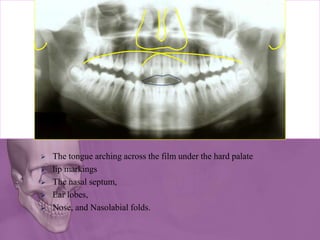

 The tongue arching across the film under the hard palate

 lip markings

 The nasal septum,

 Ear lobes,

 Nose, and Nasolabial folds.